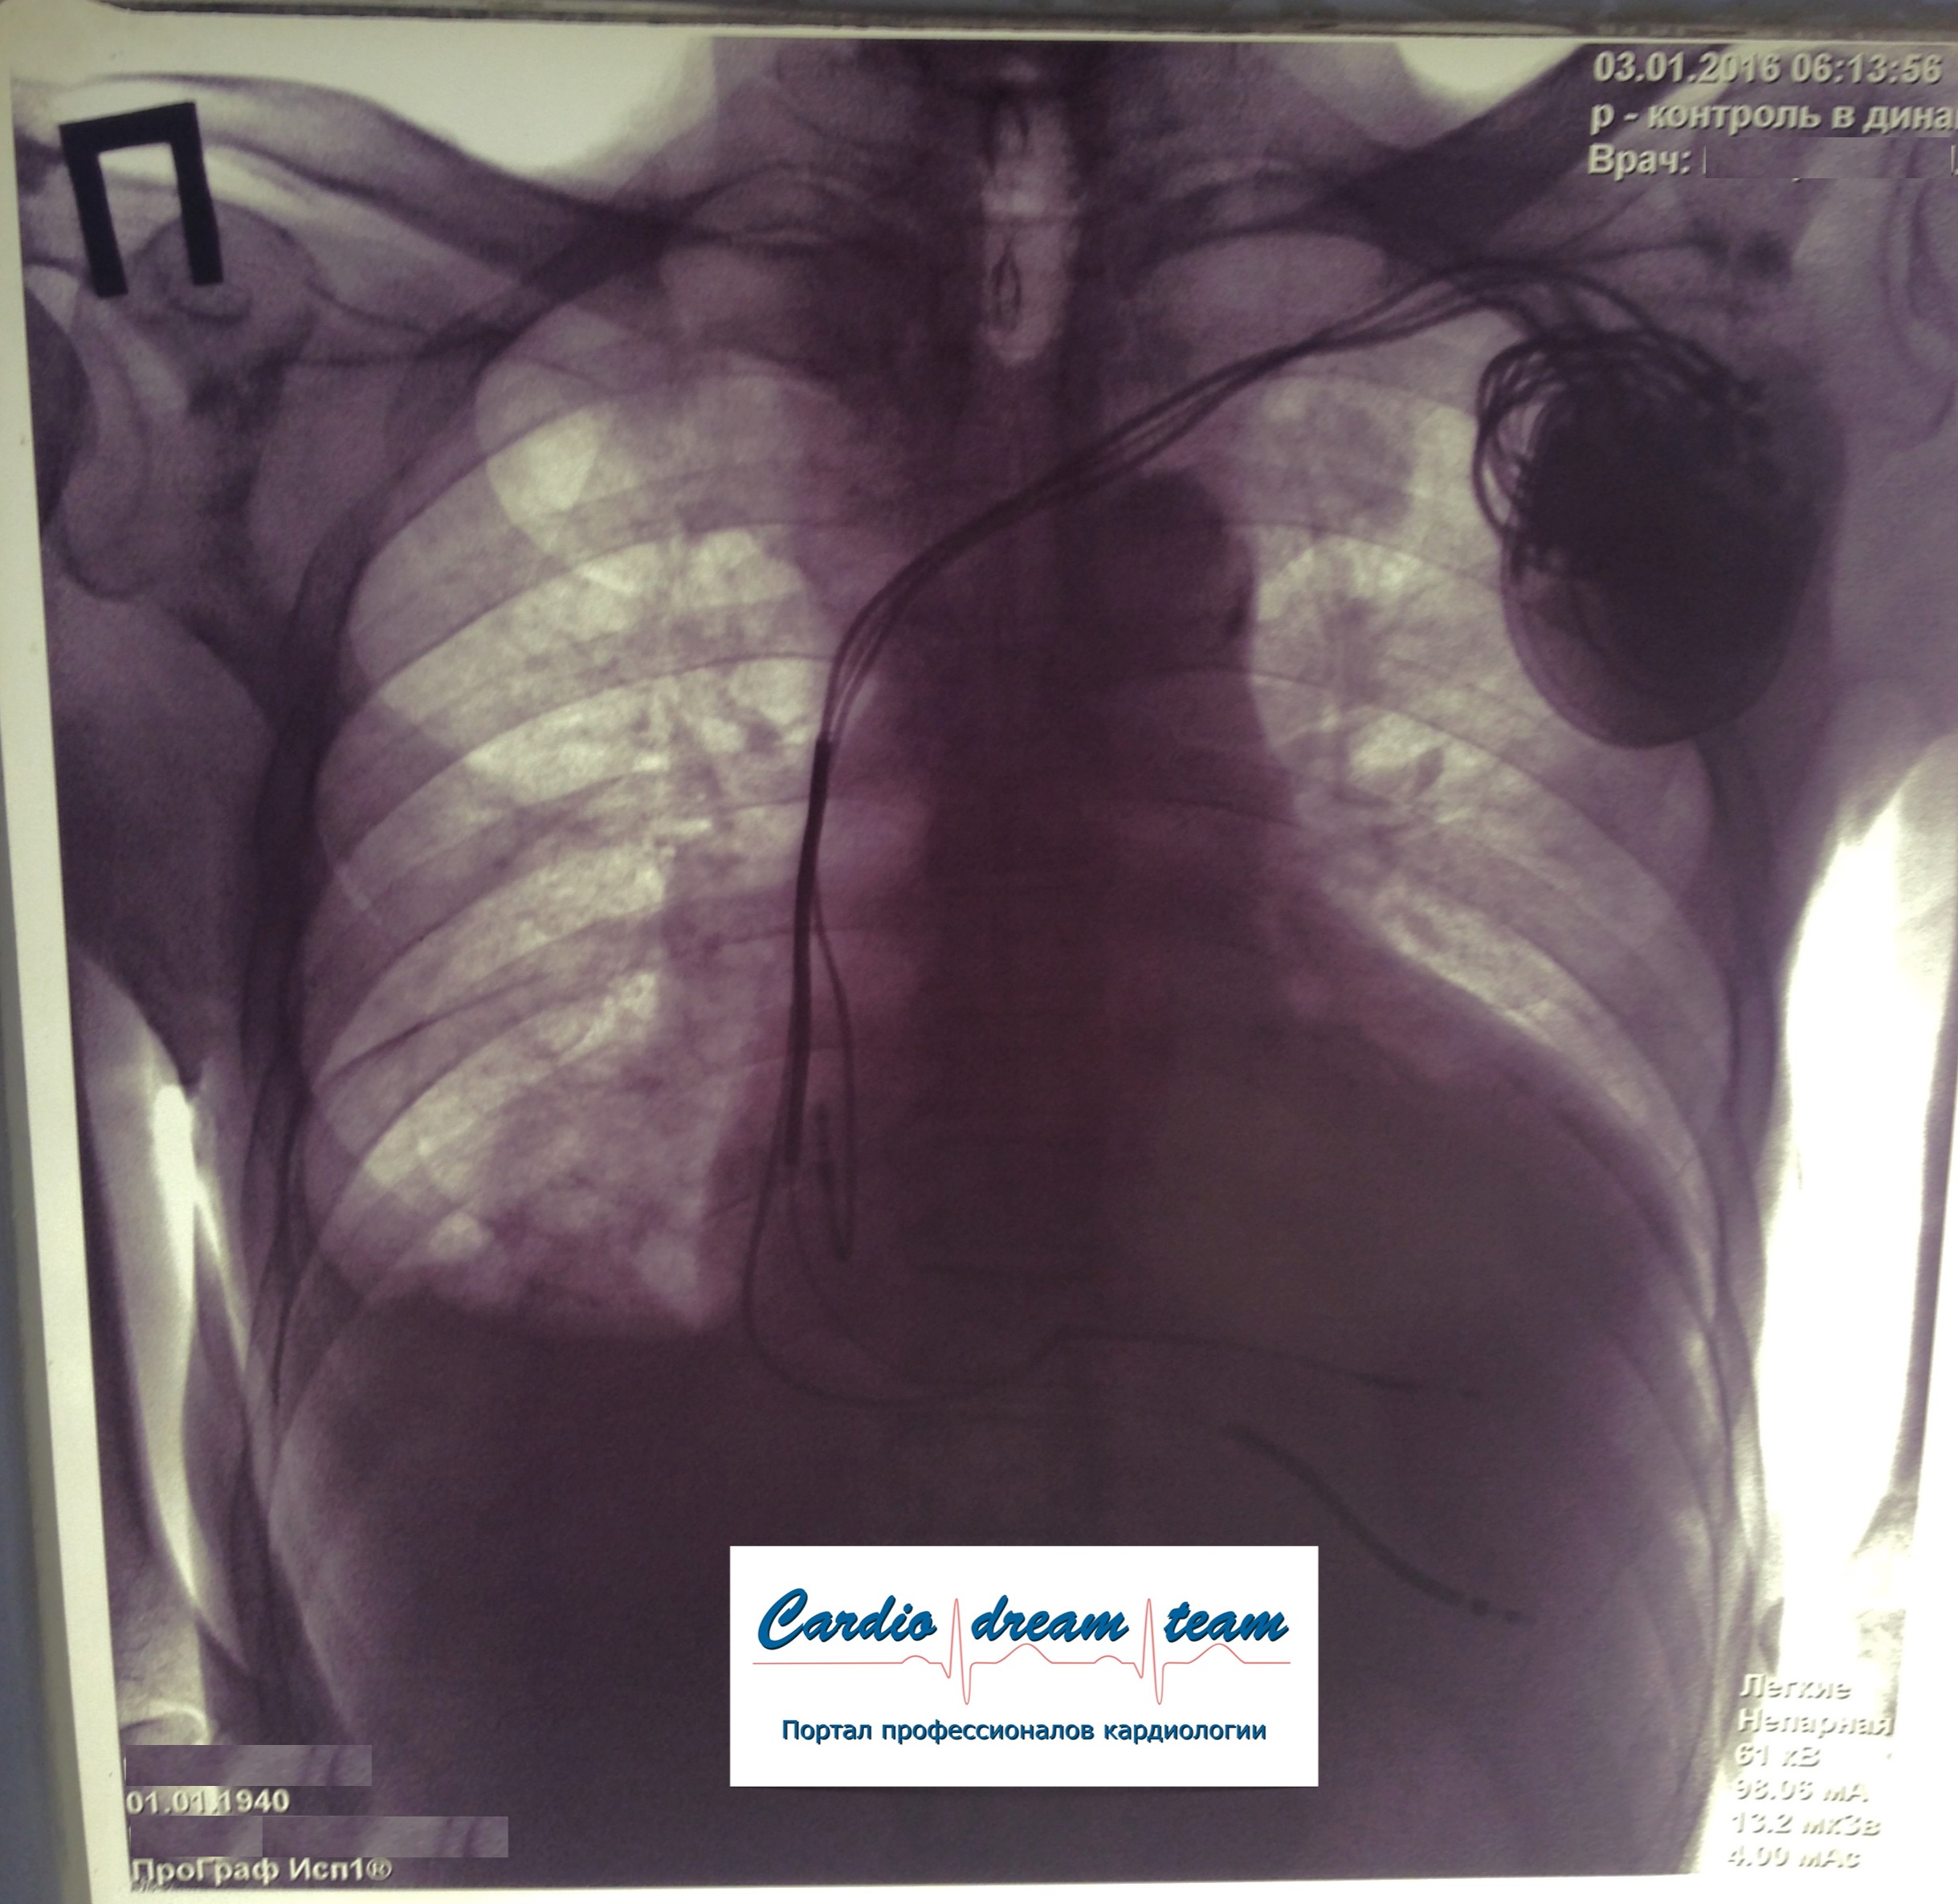

ИКД + ЭКС DDD. Когда всё на месте и всё работает.

Один желудочковый электрод подключен, другой нет.